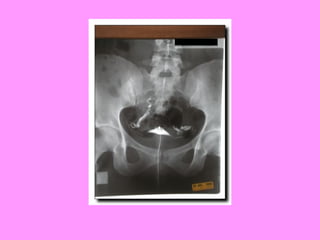

• Broad range of tests avail

– General health status checked 1st

– Pelvic examinations, ultrasound, CT scans

check for structural abnormalities

– Tubal insufflation (gas/pressure

measurement) or hysterosalpingogram (X-ray

w/ contrast material) used to check tubes

– Blood tests throughout cycle to check

hormone levels